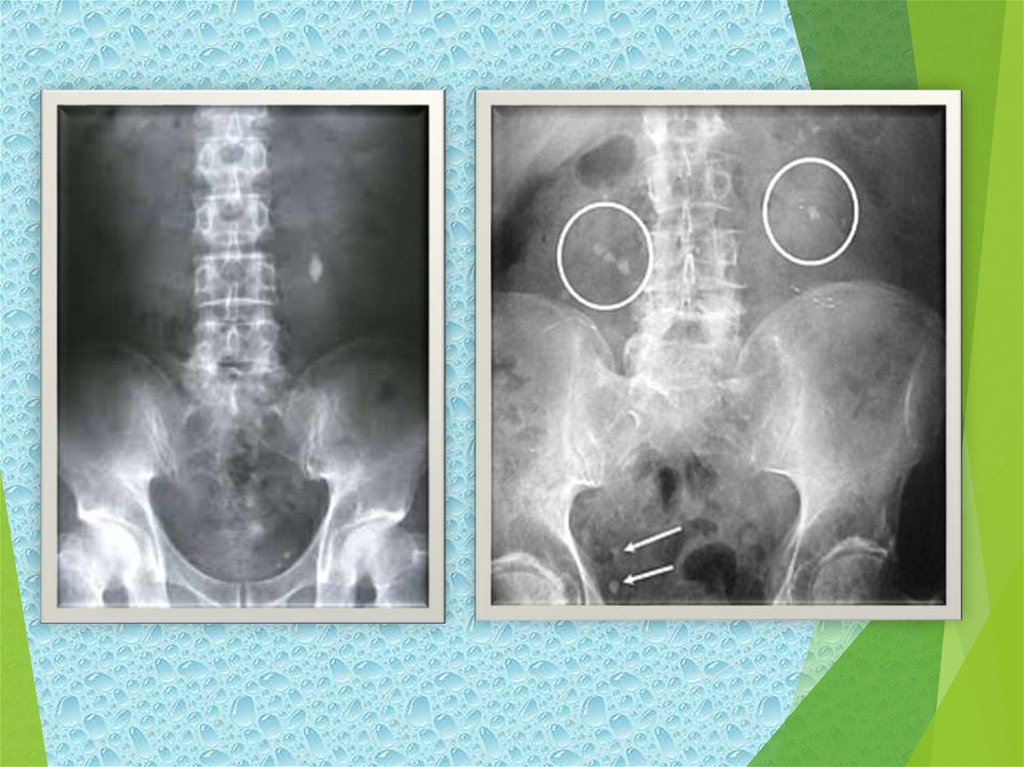

Инструменталдық зерттеулер: (рентгенологиялық белгілер - бүйрек

көлемі, R-позитивті конкремент көлеңкесі, тас есебінен түбекше мен

зəрағар толу ақауы, бүйректің қуыстық элементтерінің, зəрағардың

кеңею белгілері.

УДЗ - тастың дисталды жағында акустикалық көлеңкенің болуы,

бүйректің қуыстық элементтерінің кеңею белгілері; КТ - тастардың

кеңістіктік орналасуы, оның ішінде ұсақ, кораллтəрізді конкремент

фрагменттерімен қарым қатынас).

14. Шолу рентгенография (кальций тастары айқын (интенсивті) контрасты; цистиндік,

трипельфосфаттық жəне аралас урат-кальций тастары орташа контрасты).